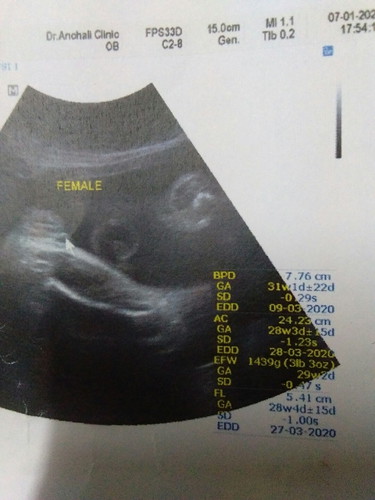

น่าจะชัวแล้วคะแม่8เดือนแล้วคะ ในใบซาว ก็ระบุเพศ แล้วว่ส ผญ คะ

แบบนี้ได้ผู้หญิงชัวไหมค้ะ